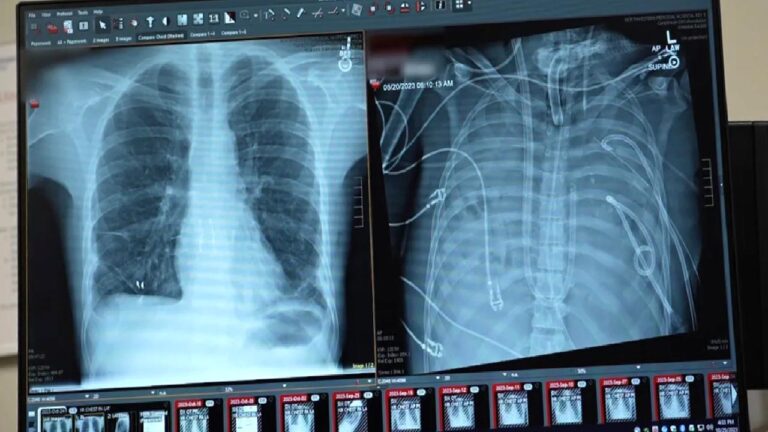

Tıp dünyasında yaşanan yani bir gelişme, biyolojik sınırların nasıl zorlanabileceğini bir kez daha kanıtladı. Şiddetli bir enfeksiyon nedeniyle akciğerleri işlevini tamamen yitiren ve adeta “eriyen” 33 yaşındaki bir hasta, organ nakli öncesinde tam iki gün boyunca akciğersiz yaşamayı başardı.

Her şey sağlıklı bir erkeğin Influenza B virüsüne yakalanmasıyla başladı. Başlangıçta basit bir grip gibi görünen durum, kısa sürede akut solunum yetmezliğine dönüştü ve hastaneye ulaştığında durumu artık kritik bir noktaya gelmişti. Antibiyotikler ve geleneksel oksijen tedavileri, akciğerlerdeki yıkımı durdurmaya yetmedi. Hastanın akciğerleri o kadar ağır hasar almıştı ki, hem kalbi hem de böbrekleri iflas etmeye başladı. Operasyonu yöneten Profesör Ankit Bharat, hastanın hastaneye ulaştığı an kalbinin durduğunu ve akciğer dokusunun geri dönülemez şekilde bozulduğunu belirtiyor. Bu aşamada klasik yöntemler yetersiz kalınca, tıp ekibi radikal bir karara imza atarak, iltihap odağı haline gelen akciğerleri tamamen çıkarmayı ve hastayı yapay bir düzenekle hayatta tutmayı denedi.

Akciğerlerin vücuttan çıkarılması, enfeksiyonun kontrol altına alınması için tek yol haline gelmişti ancak bu durum devasa bir teknik sorunu da beraberinde getirdi. Kalp ve akciğerler birbirine kopmaz bağlarla bağlı olduğu için, akciğerler olmadan kanın oksijenlenmesini sağlamak ve kalbin zayıflamış ritmini korumak neredeyse imkansız bir görevdi. Uzmanlar, kanı vücut dışında oksijenlendiren mevcut teknolojileri daha da geliştirerek, kalbin üzerindeki basıncı dengeleyen özel bir sistem kurdu. Bu yapay düzenek, iki gün boyunca hastanın kanındaki karbondioksiti temizleyip oksijen sağlayarak diğer organların iyileşmesine zaman tanıdı.